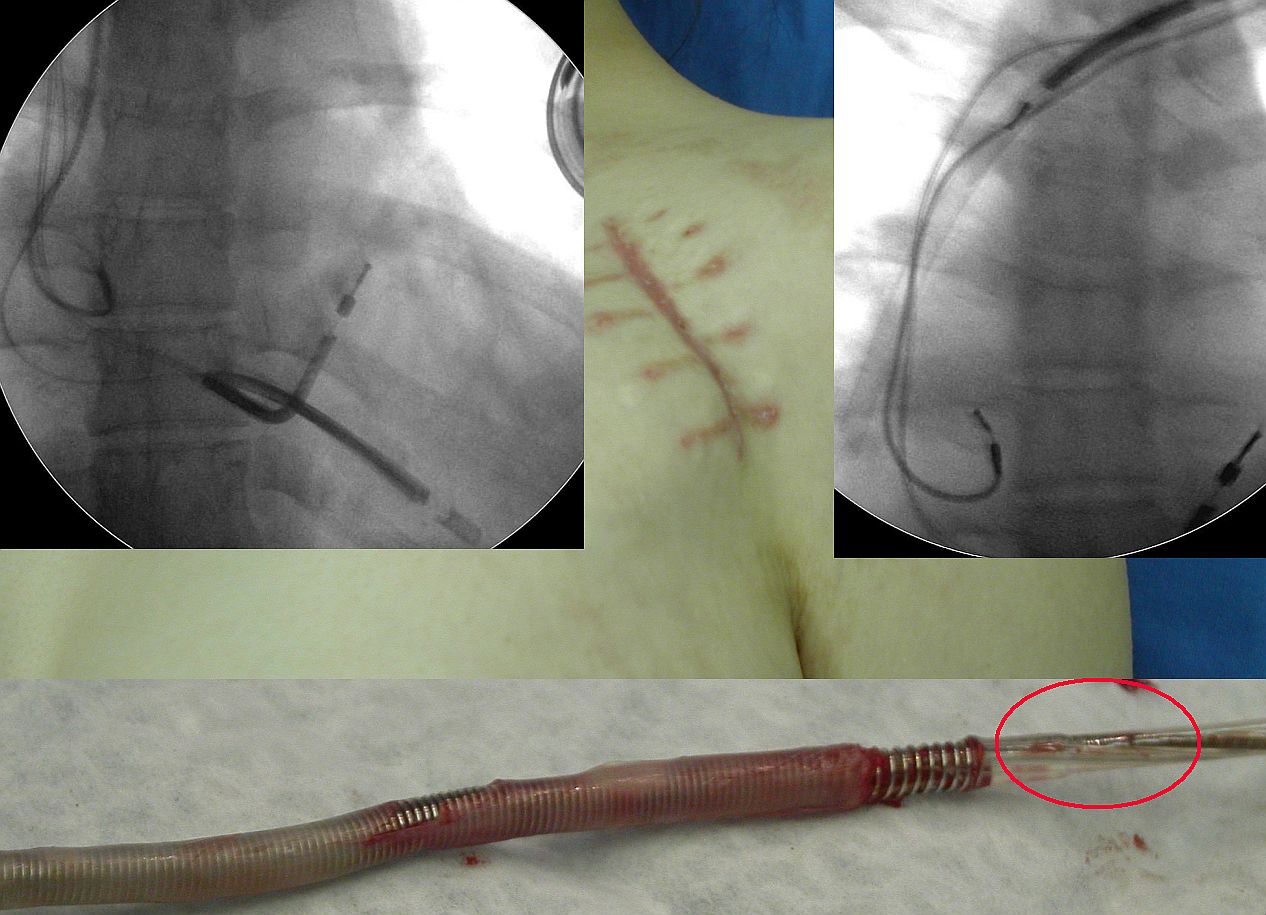

znacznie poważniejsze. Elektrody stymulatorowe, w większości

konstrukcji koaksjalnej, mają dużo wolnych przestrzeni

wewnętrznych. Najważniejsza z nich to przestrzeń wokół

spirali zewnętrznej, pod zewnętrzną osłonką

elektrody. Przetarcie osłonki z osłonięciem spirali

powoduje, że do tej przestrzeni wnika krew. Przestrzeń

ta często miewa połączenie z lożą stymulatora, gdzie

dochodzi również do często niewidocznych gołym okiem

mikrouszkodzeń osłonki. W przypadku miejscowej infekcji

loży, przetarta elektroda stanowi idealną autostradę

prowadzącą z loży do wnętrza serca, na której

drobnoustroje chronione są przed mechanizmami obronnymi

organizmu i antybiotykami na całej jej długości. Z

kolei w przypadku przejściowej / przemijającej

bakteriemii - drobnoustroje mogą wniknąć do tej

przestrzeni też mając idealne warunki do rozwoju. Do

postawienia tej hipotezy upoważniło nas zaobserwowanie

dwóch zjawisk: częstej obecności wegetacji w miejscu

przetarcia elektrod oraz wybitnie częstego współistnienia

zapalenia wsierdzia z przetarciem elektrod. O ile w całości

naszego materiału IZW stanowiło wskazanie do usunięcia

elektrod u 17% pacjentów, to wśród pacjentów z IZW

przetarcie osłonki elektrody z perforacją stwierdzono w

46 %, u pacjentów z infekcją miejscową - jedynie w 15%

i u pacjentów u których elektrody usuwano ze wskazań

nieinfekcyjnych (głównie nadmiar zbędnych elektrod) - w

23%. Oczywiście że jakkolwiek nie należy traktować

przetarcia elektrody jako jedynej przyczyny tzw.

odelektrodowego zapalenia wsierdzia, to jednak zjawisko to

wydaje się mieć istotne znaczenie patogenetyczne.